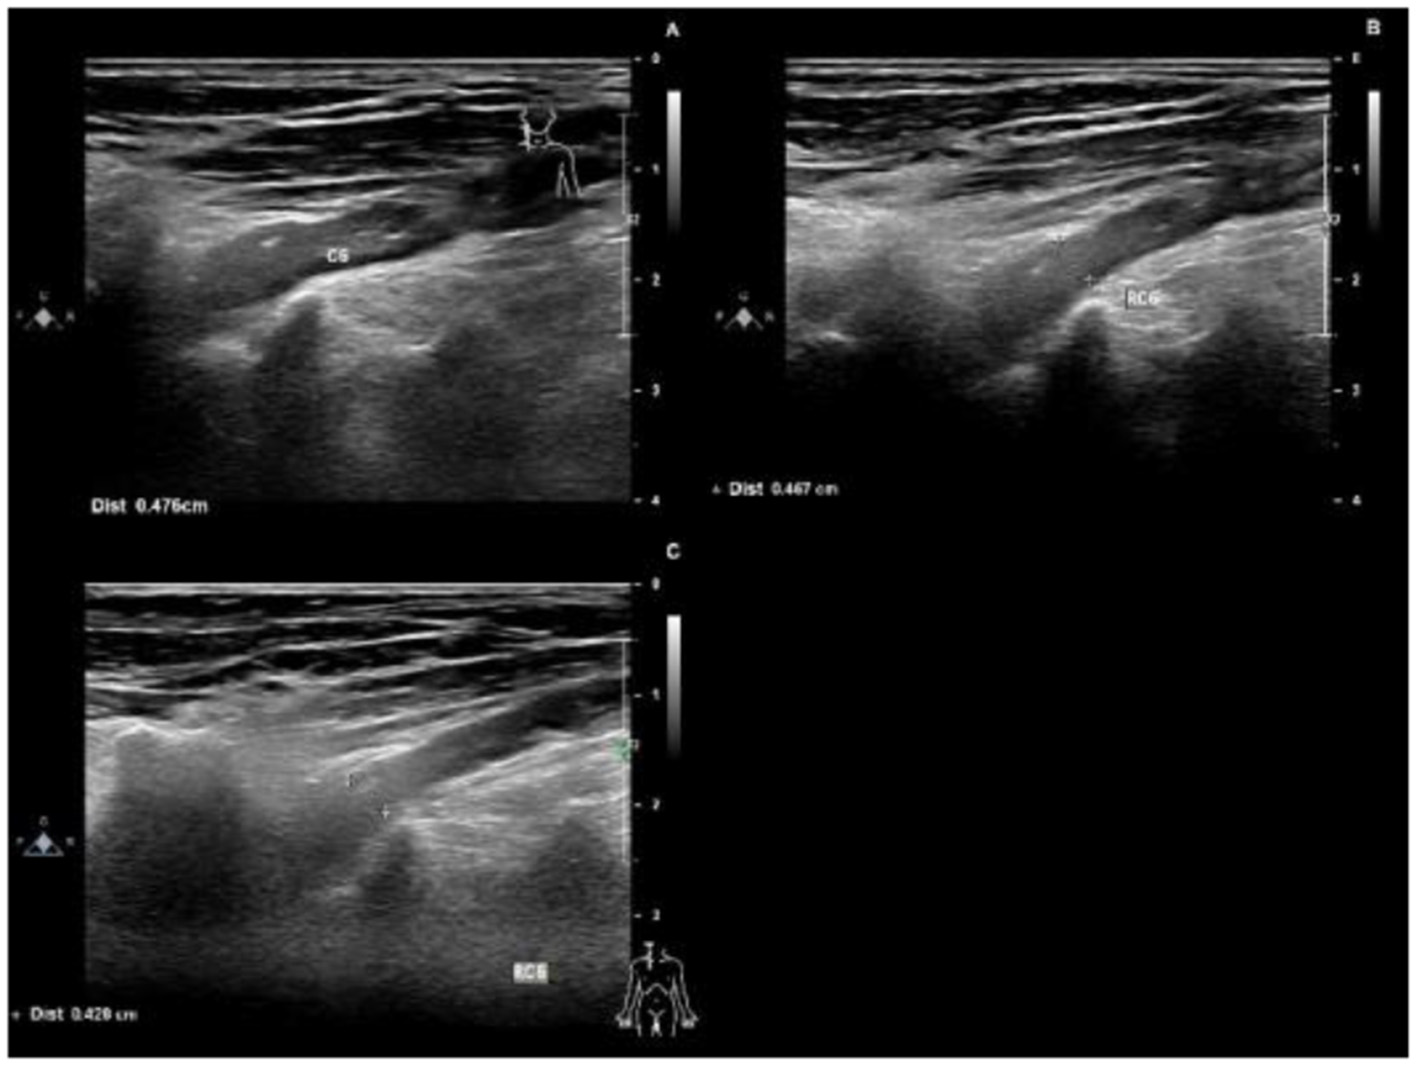

Figure 2

Ultrasounds 4 months after the onset of the disease, the right C6 nerve root was thickened, with a thickness of 0.476 cm (A). 6 months after the onset of the disease, the right C6 nerve root was thickened, with a thickness of 0.467 cm (B). 11 months after the onset of the disease, the right C6 nerve root was thickened, with a thickness of 0.426 cm (C).

Protein-cell separation is present in 80–90% of typical CIDP patients. The latest literature suggests that the reference upper limit of cerebrospinal fluid total protein (CSF-TP) should be higher than 45 mg/dl (18). The cerebrospinal fluid (CSF) protein of patients with nodopathies associated with positive anti-CNTN1 antibody is more obvious (16). In addition, MRI of CNTN1 antibody-positive patients may show symmetrical diffuse edema, thickening of nerve roots in the brachial plexus and lumbosacral plexus, as well as edema thickening of nerve roots in musculoskeletal ultrasounds. The mechanism for these may be a lack of blood-nerve barrier at the nerve roots, which are highly susceptible to damage by circulating immune antibodies. The cerebrospinal fluid protein of this patient was 618 mg/dl. MRI and musculoskeletal B-ultrasounds were consistent with the above findings. The musculoskeletal ultrasound showed no significant changes before and after treatment (Table 3). Considering that the improvements observed in auxiliary examinations lagged behind the clinical manifestations, further follow-up observations can be made.